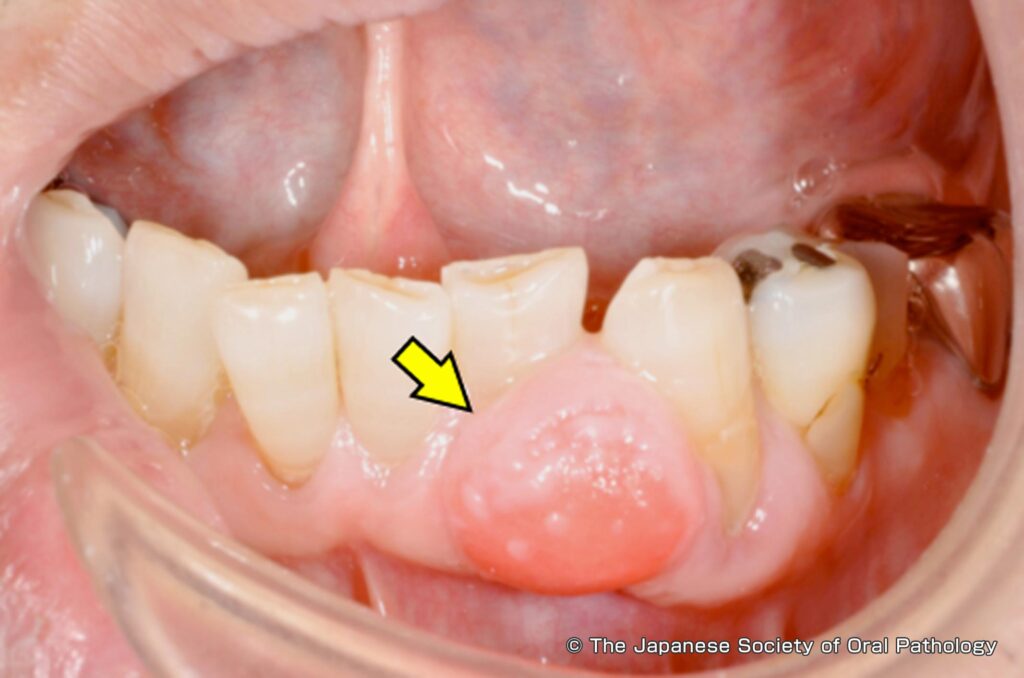

エプーリスは歯肉に発生する良性の限局性腫瘍です。エプーリスと癌の違いとしては癌のような悪性腫瘍とは異なり、エプーリスは良性の腫瘤(しゅりゅう)の総称で歯肉種・しこりとも呼ばれることがあります。 腫瘍と腫瘤どちらもよく似た言葉ですが、“腫瘍”が生体内の制御に反し細胞が自律的に過剰に増殖するのに対し、エプーリスは限局性のためそれができた場所にとどまっているのが特徴です 限局性腫瘍とは発生した場所にとどまっているできもののことです。 エプーリスは歯肉腫とも呼ばれます。 形は半月上のものなど様々なものがあり、色はピンクや赤みがかった色となることが多いです。

エプーリスができる原因は、歯肉への慢性的刺激やそれによる炎症で組織が反応するためです。 不適合補綴物、歯石などによってできてきます。 また妊娠時の女性によく見られるのは、女性ホルモンなどの内分泌異常が誘因と考えられています。

エプーリスの治療は、病変部位を切除することが基本となります。 病変そのものだけを切除すると再発することが懸念されるため、同時に抜歯を行うこともあります。 妊娠に関連したエプーリスでは、出産によって自然に退縮することが期待できます。 そのため、無治療で慎重に経過観察をすることもあります。